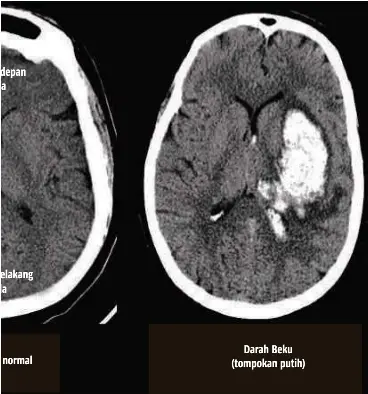

Xray Darah Beku Di Kepala

Saya mempunyai darah beku di kepala sebesar duit syiling 20 sen. Darah beku di kepala bila tidak segera diatasi bisa mengancam jiwa. Selain kesulitan bicara dan kejang kejang penderitanya pun akan bermasalah dengan penglihatannya misalnya pendangannya yang menjadi kabur.

Berdasarkan penelitian teripang emas yang dipublikasikan di situs ncbi menjelaskan bahwa biota ini memiliki antikoagulan yang cegah penggumpalan darah atau. Sedangkan darah beku di kepala yang terjadi pada bagian pusat bicara maka pasien dapat mengalami gangguan dalam berbicara. Pembekuan darah dikepala adalah adanya darah beku seharusnya mengalir pada bagian kepala baik diluar jaringan ataupun didalam pembuluh darah.

Akibatnya jantung akan berdetak lebih cepat dikutip dari bright side jumat 2 2 2018. Sakit kepala yang berkepanjangan merupakan gejala gumpalan darah di kepala yang sering diabaikan. Darah beku di kepala secara perlahan dapat menghambat kerja otak.